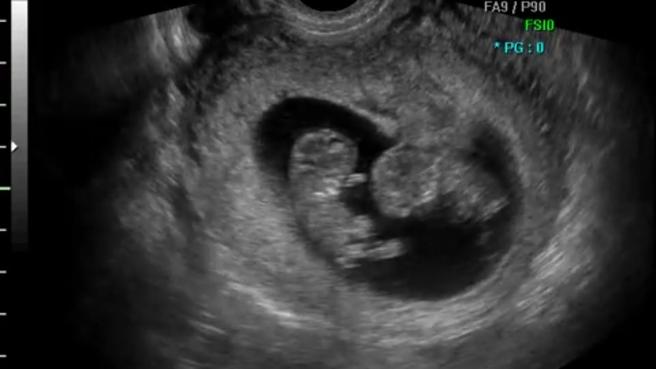

Czy to blizniaki

Dzień dobry ostanio byłam u lekarza i lekarz mi powiedział że narazie widzi jedno maleństwo . A ja widze tam dwa i nie wiem co mam myśleć potrzebuje porady.

Nie wiem gdzie i co Ty widzisz ale chyba lekarz zna się lepiej ;)

Ja widzę jedno. Poza tym bardzo słaba jakość. Może zaznacz gdzie widzisz.

Ale to tak bardziej z ciekawości bo najsensowniej to po prostu skonsultować się z innym lekarzem.